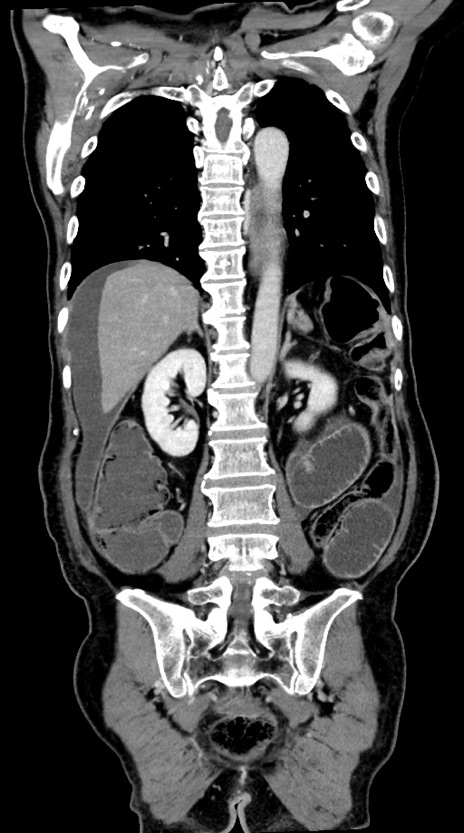

症例28(冠状断像)

【症例】60歳代男性

【現病歴】胃癌にて胃全摘後。食思不振が悪化し、夜中に嘔吐することがある。

【既往歴】胃癌、胃全摘、脾摘、胆摘後